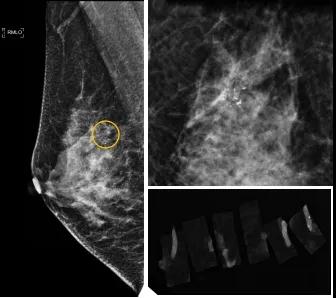

46歲的某女士在西安國際醫(yī)學(xué)中心醫(yī)院體檢時,行乳腺X線攝影(俗稱鉬靶)發(fā)現(xiàn)右乳可疑簇狀鈣化,分布范圍不到1厘米,臨床觸不到,超聲很難發(fā)現(xiàn),但是這種鈣化風(fēng)險比較高,依據(jù)國際BI-RADS指南需要明確病理!

西安國際醫(yī)學(xué)中心醫(yī)院影像診療中心陳寶瑩副主任帶領(lǐng)的團隊,采用全數(shù)字化乳腺X線三維立體定位系統(tǒng)可實施。這個團隊的成員大部分來自知名三甲醫(yī)院,有著十余年影像引導(dǎo)下乳腺介入診療的經(jīng)驗,X線引導(dǎo)穿刺定位和活檢例數(shù)居西北前列。為減少患者創(chuàng)傷,在詳細(xì)判讀了患者資料,并與患者及甲乳外科劉曉敏主任充分溝通的基礎(chǔ)上,團隊確定采用全數(shù)字化乳腺X線三維立體定位系統(tǒng)下實施粗針活檢。

當(dāng)天,乳腺X線三維立體定位系統(tǒng)清晰顯示出了所有鈣化。為了獲取充足的組織量,保證病理診斷的準(zhǔn)確性,團隊選用14G穿刺針并多點、多角度取材,組織取出后,又立即在高清標(biāo)本攝影系統(tǒng)中進(jìn)行投照,從而確定了取出組織中具有足夠的可疑鈣化。整個過程患者無任何不適,活檢結(jié)束后即回家觀察。